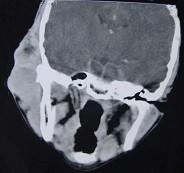

问题 女性,19岁,右侧面颊部肿胀1年,CT检查如图所示,请选择最佳答案()

选项 A.右颊部神经纤维瘤 B.右颊部血管瘤 C.右颊部脂肪瘤 D.右颊部横纹肌肉瘤 E.右颊部血肿

答案 B